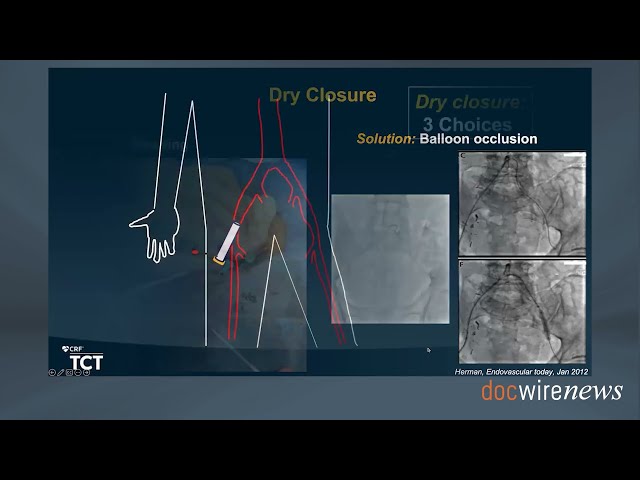

Dr. Lichaa details his presentation from TCT 2023, which covers tips and tricks for dealing with peripheral challenges.